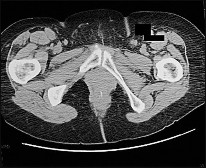

Figures 24a and 24b are the right femur radiograph and bone scan of a 71-year-old man with longstanding metastatic prostate cancer who has experienced increasing right thigh pain for 2 months. The pain is worse with activity and is alleviated with rest. He experienced similar pain in his left thigh 18 months ago and subsequently sustained a left subtrochanteric femur fracture after a low-energy twisting injury. He was successfully treated with an intramedullary nail. He had been receiving zoledronic acid for 4 years prior to the fracture. This patient’s history includes heavy steroid use. His current symptoms are most likely the result of

This patient’s history and imaging are most consistent with an atypical femoral fracture attributable to impaired bone remodeling. Both bisphosphonates and denosumab are associated with atypical

femur fractures. Atypical fractures may occur in the diaphysis and the subtrochanteric region. The patient’s prior femur fracture was attributable to bisphosphonate (zoledronic acid) use. Bisphosphonates directly inhibit osteoclasts. He subsequently experienced a long symptom-free interval during which he took denosumab, which is an indirect osteoclast inhibitor. The imaging is not consistent with a symptomatic prostate metastasis. L4 radiculopathy may cause thigh pain, but there is no evidence (other than the mention of spine metastasis) supporting this diagnosis.